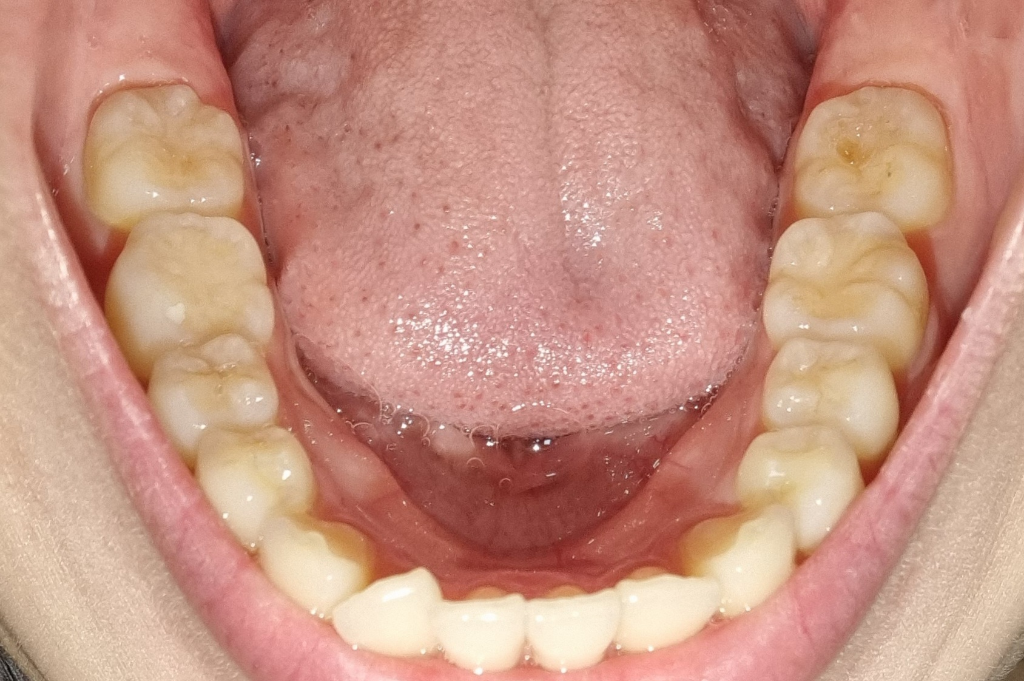

치아마모가 심한편인가요? 관리를 어떻게 해야할까요?

1. 치아 마모가 심각한 수준일까요?

• 3번 째 사진

사진상으로 보면 치아 마모상태가 심한거 같진 않습니다. 턱관절이 아프거나 그럴경우에는 스플린트나 보톡스 치료를 받으시면될것같습니다.

1. 사진상 치아 마모가 아주 심한 수준은 아니라고 판단됩니다.